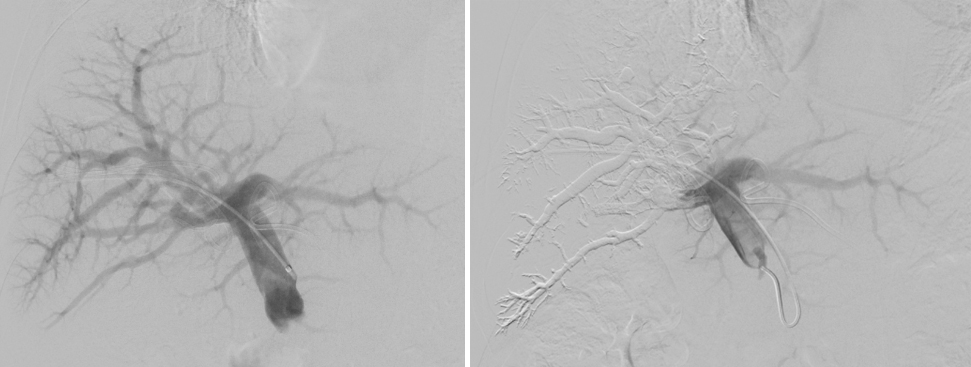

PVE术前门静脉造影(左)      PVE术后显示右侧门静脉栓塞完全(右)